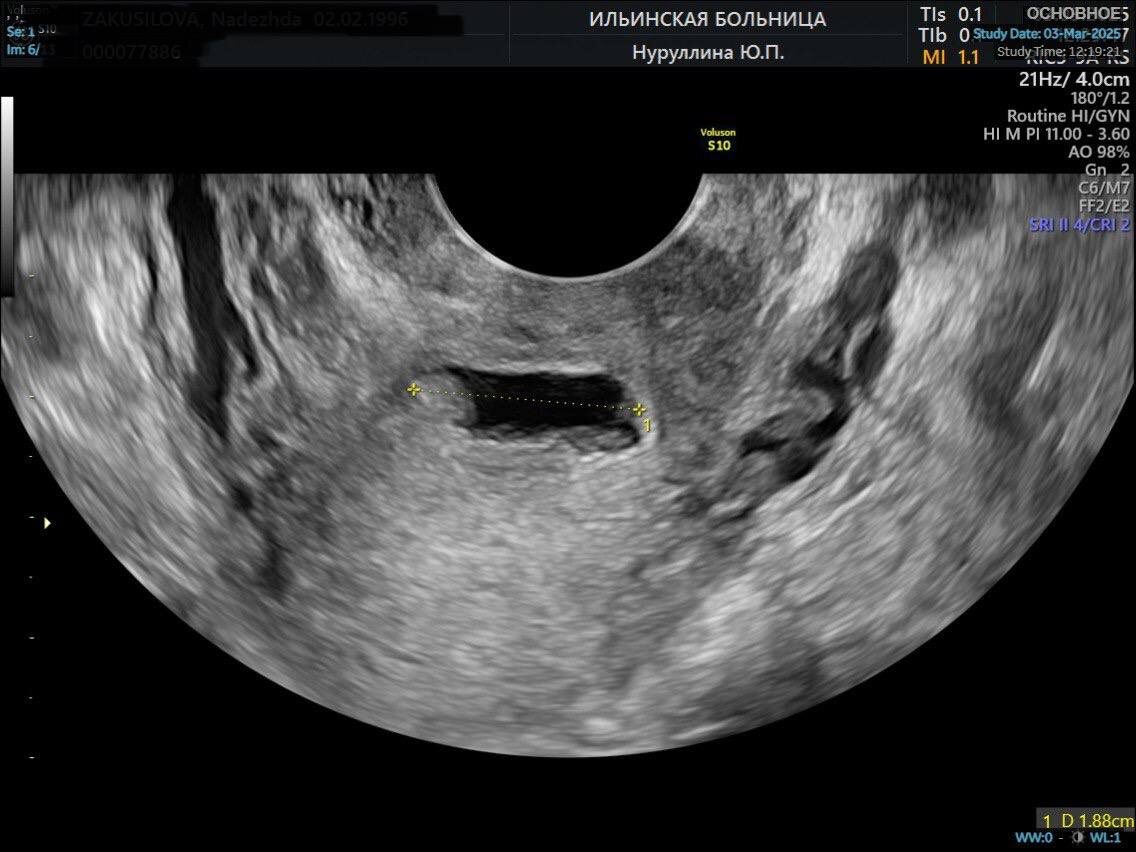

УЗИ матки до операции

Если женщина планирует беременность, крайне важно точно измерить толщину резидуального (оставшегося целого) миометрия (мышечного слоя стенки матки).

При выявлении истончения миометрия менее 3 мм над рубцом и наличии у женщины репродуктивных планов необходимо выполнить операцию — метропластику. Это лапароскопическое (через проколы в брюшной стенке) иссечение старого истончённого рубца на матке с наложением новых швов и формированием нового состоятельного рубца.

Пациентка приехала к нам из другой страны. Ей 27 лет. У неё была 1 беременность, которая закончилась операцией кесарева сечения. Спустя несколько лет пациентка приняла решение о повторном планировании беременности, и при обследовании перед планированием по данным УЗИ у неё выявлены признаки ниши в области рубца на матке.